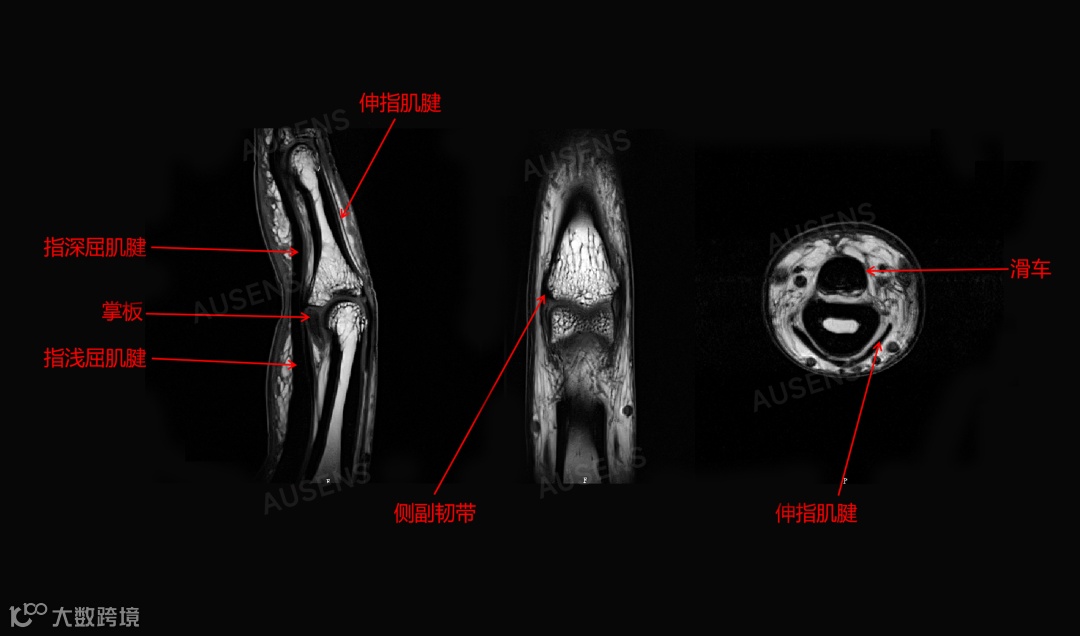

显微级分辨率(可达 90 微米),清晰显示四肢关节的骨骼、软骨、韧带、神经、血管等组织,在早期诊断骨关节炎、软骨损伤等常见疾病中发挥重要作用。

与常规 3.0T 通用型磁共振相比,奥新医疗 3.0T 四肢关节磁共振成像系统的磁场均匀性、梯度场强度、梯度切换率等关键参数显著提升,图像更清晰精准,可更好显示关节软骨、韧带、骨小梁等细小结构,减少漏诊和误诊,为临床提供可靠依据。

临床可根据精细影像信息(如损伤程度、范围及与周围组织关系),精确制定治疗方案。对手术患者,可辅助规划手术入路、选择术式和植入物,提高手术成功率。